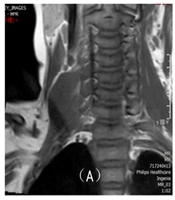

Magnetic Resonance Imaging (MRI) Features and Diagnostic Accuracy in Pediatric Brachial Plexus Neuropathy: A Retrospective Analysis